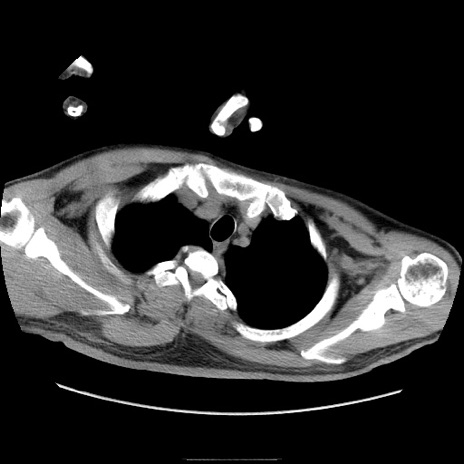

症例22(横断像)

【症例】50歳代男性

【主訴】腹痛

【現病歴】AVMからの被殻出血のため回復期リハ病棟入院中。 本日午後3時頃急に下腹部痛が出現した。

【既往歴】AVM、被殻出血、虫垂炎、高血圧

【身体所見】意識晴明、左半身不全麻痺、会話の理解は良好、36.5°C、腹部:膨隆、全体に板状硬、下腹部正中に圧痛点あり、反跳痛-、筋性防御不明、右下腹部にope scar

【データ】WBC 9400、CRP 0.06